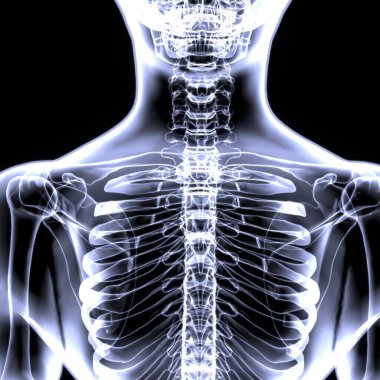

İnsan iskeleti anatomisi Scapula Kemiği Tıbbi Konsept için 3D Hazırlama

İskeletanatomiçene kemiğiyarım ayboyunlomberetmoidcapitateAltkısmınıHamate3d oluşturmaGöğüs kafesi3B illüstrasyoncarpalsağız sapımetakarplaralın kemiğiApendiküleruyluk kemiğioksipital kemikBurun kemiğikemiğigöğüs kemiğinin gövdesiayak kemikleriyarıçap kemiğiparietal kemikeksenel iskeletKalça kemiğilacrimal bonepalatine boneproximal phalangesinferior nasal conchaintermediate phalangesdistal phalangesclavicle bonekaval kemiğiBurun kıkırdağıkol kemiğikürek kemiğiBenzer İçerikler